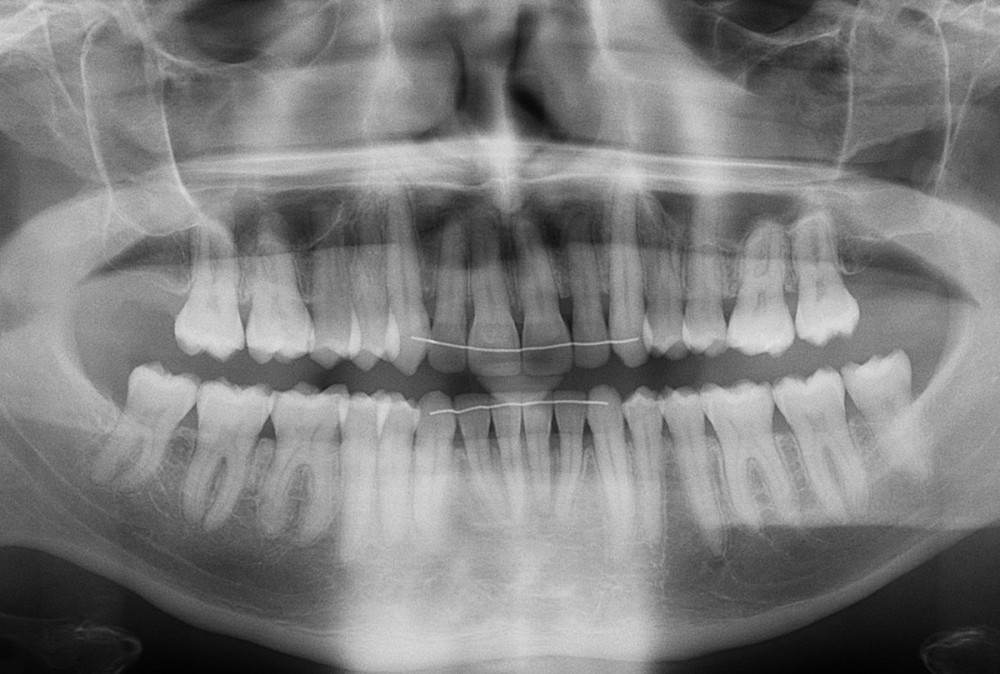

Diagnostic (fig. 1a-i)

Le patient consulte initialement pour des défauts d’alignement. L’examen clinique confirme l’existence d’un encombrement antérieur bimaxillaire, mais révèle aussi la présence d’une Classe II dentaire sévère, d’une exoclusion de la 27 et de troubles parodontaux (peu ou absence de papilles inter-dentaires). Sur le plan squelettique, le patient est relativement équilibré avec un profil harmonieux.